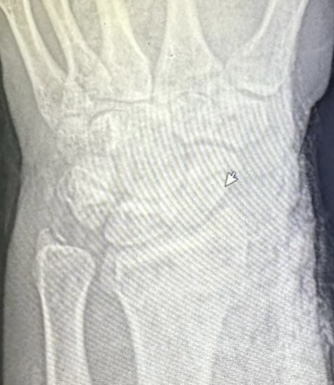

Клинический случай: внутрисуставной перелом дистального метаэпифиза лучевой кости — до операции